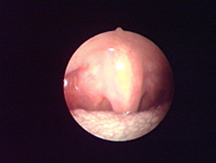

適于精確損毀破壞內(nèi)部組織。

適合于精準(zhǔn)的點(diǎn)狀凝血。

適合于在重要的部位實(shí)現(xiàn)凝血。